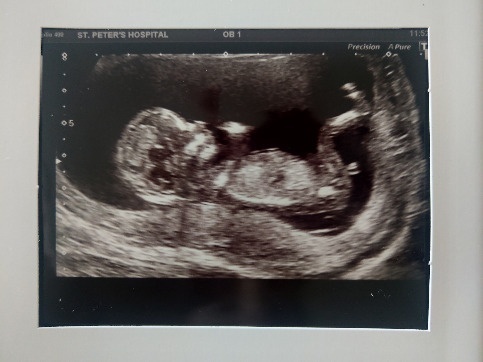

Mi most végeztünk az ultrahanggal, kombinált teszttel. Méretek alapján 13+2 (12+6 volt). Úgyhogy még előrébb hozták a születést december 27 lett. Minden tökéletes volt nagyon aktívan táncolt meg bokszolt.. Kis cuki, megnevettetett, annyira kis izgága. Ja a tarkóredő 1.50 mm. Azt mondta az ultrahangos, ezt max a vér eredmény ronthatja le, de remélem, nem így lesz.

Érdekes, teljesen nyugodtan mentem be, nem izgultam egyáltalán. Lehet a rosszulléttől nem volt energiám még idegeskedni is.. Megpróbálok képet feltenni. Van videó is, kis cukin rugdos.

Nokli,nagyon jó képet csináltak a babciról.Már milyen szépen meg van mindene.Teljesen baba már!

Azert milyen durva,hogy pl Nokli a te babádnak a tarkóvastagsága 1,5mm az enyemnek 2,3mm És neked még 2 nappal idősebb is a babód..Alacsony kockázatú lettem,de ez a 2,3mm picit zavar..

Nokli neked milyen arány lett?